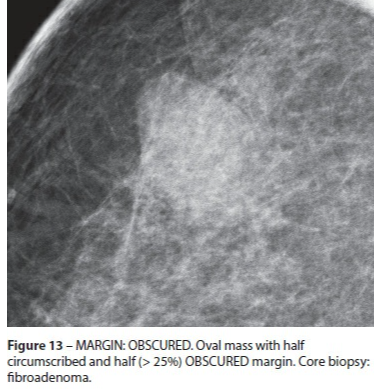

Obscurcie

- <75% de bien délimitée

- Obscurcie par du tissus glandulaire ++